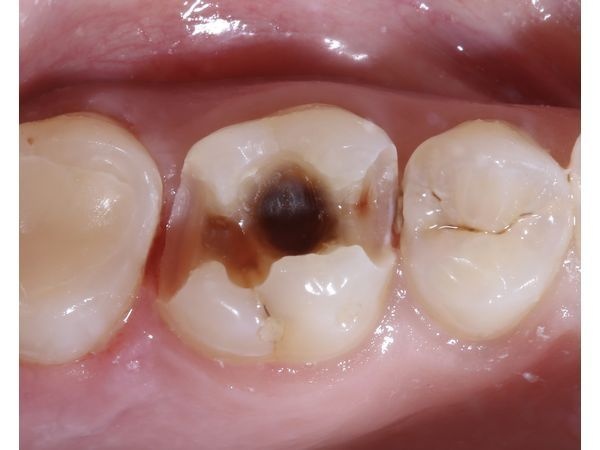

- несостоятельную пломбу с нарушением краевого прилегания и рецидивом кариеса в зубе 1.6.

КТ верхней и нижней челюсти показала тень глубокой кариозной полости под несостоятельной пломбой в правом верхнем моляре.

- удалили старую пломбу и кариозные ткани с сохранением нерва;

- проверили, все ли мёртвые ткани были удалены;